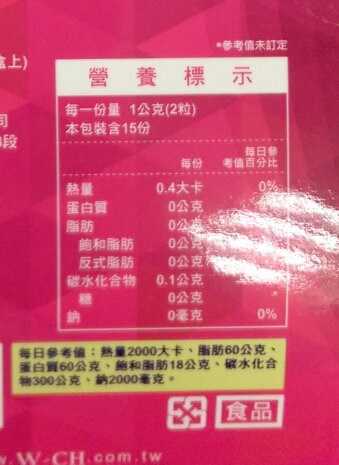

Supercut塑魔纖立塑膠囊的成分有:瓜拿那萃取粉、肉桂萃取粉、辣椒萃取物(唐辛子)、吡啶甲酸鉻、番瀉葉粉末、玉米澱粉、氧化鎂、二氧化矽。

食用方式:早晚餐前30分鐘各1粒,每日不超過2粒。(多食無益)

番瀉葉萃取物每日食用限量為12mg以下,

番瀉葉萃取物每日食用限量為12mg以下,